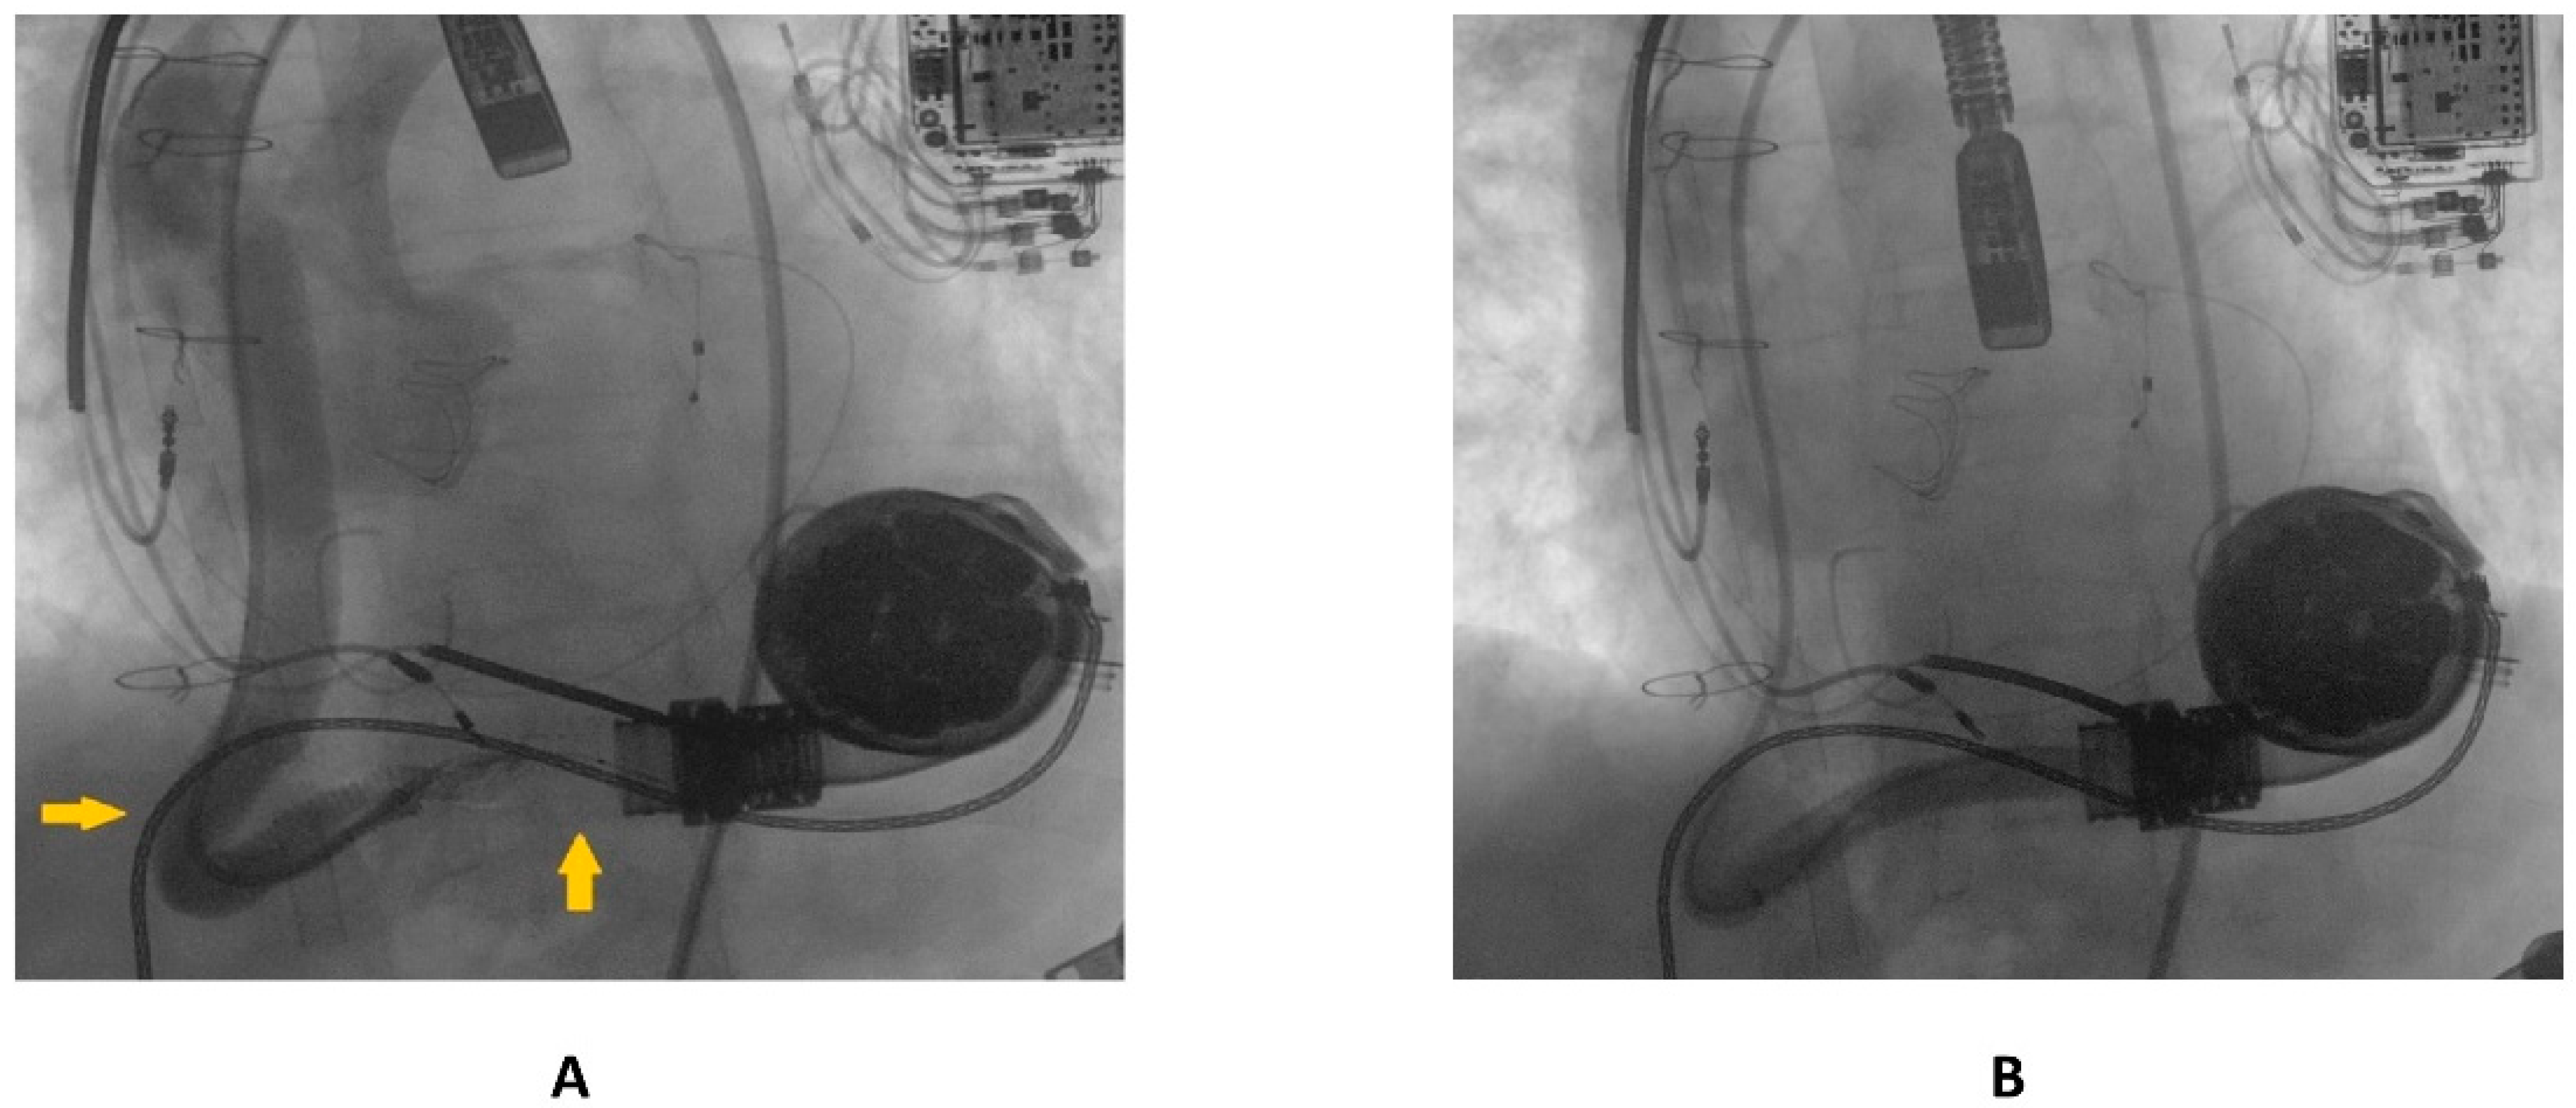

A 69 year old male with advanced HF (LV ejection fraction: 25%) due to severe familial dilated cardiomyopathy was admitted to our emergency department, complaining of severe dyspnea and asthenia. The symptoms had started one week previously and had progressively worsened. Three years before, the patient had undergone surgical aortic valve replacement for severe aortic regurgitation (Inspiris Resilia TM 26 mm, Edwards Lifesciences LLC, Irvine, CA, USA) combined with a tricuspid valve ring annuloplasty (Contour 3D TM, Medtronic, Dublin, Ireland) and followed by LVAD implantation (HeartMate III TM, Abbott, NC, USA) as a destination therapy. One year after this, the patient experienced LVAD failure caused by a proximal thrombosis of the outflow graft, which was effectively treated with a percutaneous intervention using a 10 × 59 mm balloon-expandable covered stent (ADVANTA V12-8 Fr compatible covered stent, Getinge AB) [8]. In Figure 1A,B pre- and postprocedural angiographies of the first procedure are shown.

Figure 1.

(A) preprocedural angiography of the first outflow graft obstruction episode (yellow arrows highlighting the kinking site and proximal thrombosis location); (B) result following the first percutaneous intervention.